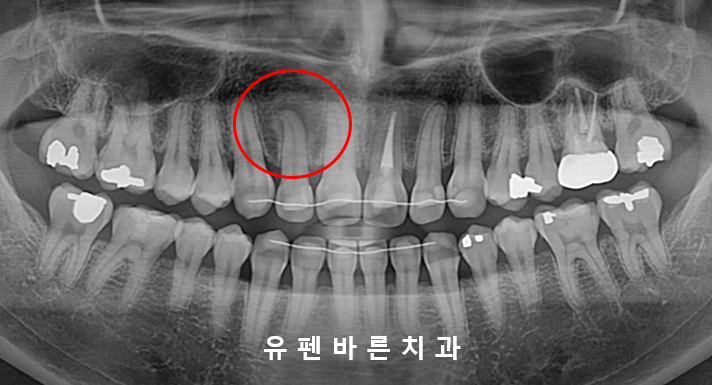

엑스레이를 찍어보니

특정적으로 많이 닿고 있는 부분에

뿌리 끝 염증이 생겨 있었어요 T_T

오른쪽 사진의 2번치아 보이시나요?

더 자세히 살펴보기 위해 작은 엑스레이를 찍어보았더니

눈에띄게 뿌리끝이 검은색 염증으로 둘러쌓여 있네요.